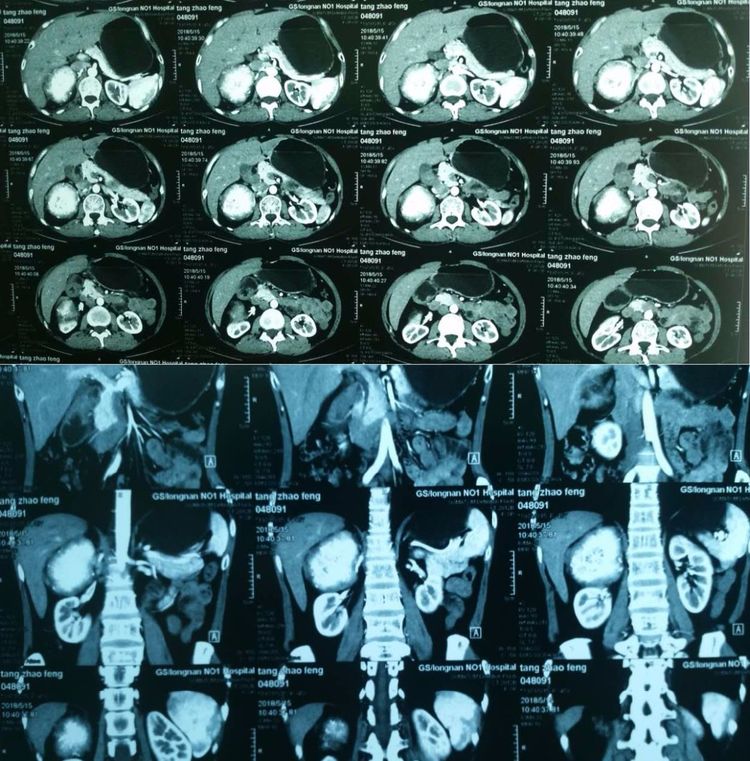

增强CT扫描明显强化

结合检查结果,考虑患者隐匿性嗜铬细胞瘤可能性大,李朝明主任立即组织全科医生会诊讨论,明确手术指征后,决定为患者实施腹腔镜下肾上腺肿瘤切除术。手术在兰大二院泌尿外科教授段建敏、王家吉的指导下顺利进行,术中见患者右肾上腺肿物与下腔静脉及周围组织黏连严重、空间狭小、少量出血、肿瘤滋养血管丰富等情况,手术困难加大,李主任立刻利用超声刀和吸引器分离肿瘤,彻底止血,经过4个多小时的手术,肿瘤被完整切除。术后患者恢复良好,现已康复出院。

术后病检:炎性肌纤维母细胞瘤伴钙化